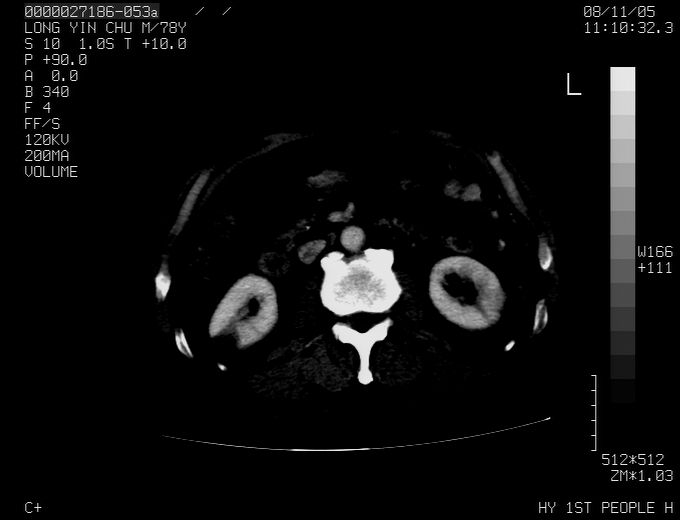

标题: CT16532:M78Y,肝脏病变,请会诊

腹胀,腹痛就诊,男性,78岁,外院b超未见异常。

考虑弥漫性肝癌并脾及双肾转移.双侧胸水.

图片质量欠佳:多考虑:左侧肾癌。脾脏转移!胸膜转移!

肝脾肾转移瘤可能性大,左肾不除外梗塞,双侧胸水

考虑肝癌并双肾及脾脏转移;双侧胸腔积液。